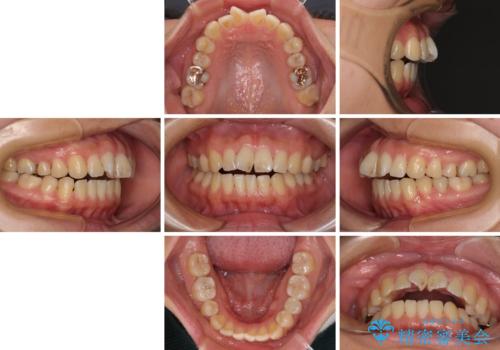

- 下顎小臼歯が欠損しており、さらに上顎が全体的に突出していることを気にして来院された患者様です。

下顎は片方の小臼歯が欠損していたため、正中がずれた上に、上下前歯が接触していない状態でした。